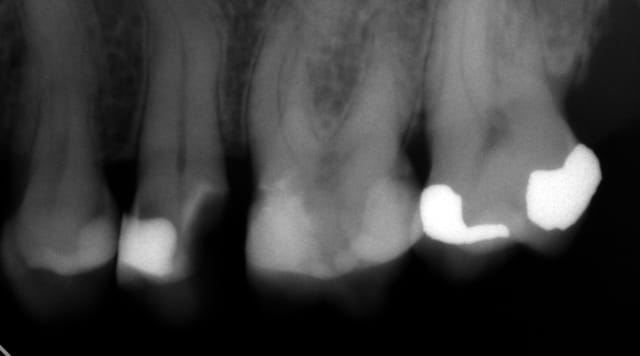

Meme si on peut douter d'une conservation pulpaire dans ce cas (et pourquoi pas des onlays sur dents dépulpées ?) il n'y a aucun doute vu les remboursements ridicules de la sécu et de la mutuelle en matière d'onlay quand au choix du patient versus inlay core ceramo metal. -))))

Il va de soit qu'en cas d'acceptation du devis d'onlays les cavités d'accès pour les endos ne ressembleraient pas à ca ! -)))